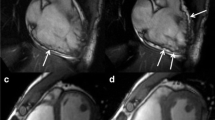

The electrophysiologic substrate of sustained VT in the setting of structural heart disease is usually represented by scar-related reentry, and the destruction of this substrate can potentially prevent VT (Fig. 10.2). The EAM substrate typically involves the basal perivalvular region of the LV and the interventricular septum with a high prevalence of midmyocardial or subepicardial substrates. Two typical scar patterns (anteroseptal and inferolateral) are found in up to 90% of patients with DCM and VT [66, 76]. Two VT morphologies are usually seen in presence of anteroseptal substrate: RBBB with inferior axis and positive concordance throughout the precordial leads or LBBB with inferior axis and early (≤V3) precordial transition (Figs. 10.3 and 10.4) [76]. Occasionally, VT arising from the septum may also present a characteristic precordial transition pattern break in V2 with a predominant R wave in V1 and V3 but an abrupt loss of the R wave in lead V2 due to an exit close to the anterior interventricular sulcus (opposite to lead V2) [66, 77]. A predominant inferolateral substrate can instead be identified in about half of the patients, and, in the majority of them (about 60%), the critical VT sites are located on the epicardium. These patients typically present VTs of RBBB morphology with right superior axis and late (≥V5) precordial transition (Fig. 10.5) [76]. The distinction between these two patterns is of great clinical value in terms of both procedural planning and outcomes. In patients with a predominant anteroseptal substrate, an epicardial approach is largely unnecessary, and the complex local anatomy (i.e., proximity to coronary vessels, presence of epicardial fat) usually limits the possibility to perform CA. Conversely, an epicardial approach is often required to achieve VT control in patients with a predominant inferolateral pattern. Even if epicardial coronary vessels and the phrenic nerve may obstacle epicardial CA in patients with inferolateral substrate, these patients typically have a more favorable outcome (75% vs. 25% VT-free survival at 1.5-year follow-up) and a lower need for redo procedures (7% vs. 59%) compared to patients with anteroseptal substrate [69]. In patients with septal VTs, the intramural location of the substrate can be difficult to address and may require sequential LV and right ventricular (RV) CA as well as the use of high RF energy potentially leading to collateral injury of the conduction system. A series of different approaches like bipolar RF ablation, high-intensity focused ultrasound, retractable needle ablation, and intracoronary ethanol ablation have been described to overcome the aforementioned limits, but none of them is currently available in routine clinical practice.

Example of endocardial (a) and epicardial (b and c) substrate modification in a patient with minimal endocardial substrate and typical inferolateral epicardial substrate. Black dots (b and c) indicate abnormal electrograms. Coronary angiography was performed to confirm safe distance of the ablation sites on the epicardium from the major coronary vessels (Reproduced with permission from Muser et al. [58])

Example of a 50-year-old man with mildly dilated cardiomyopathy and left ventricular (LV) ejection fraction of 40% presenting with recurrent ventricular tachycardia (VT) despite antiarrhythmic drug therapy with amiodarone and mexiletine. Baseline 12-lead ECG (a) shows a VT with right bundle branch block morphology and left superior axis consistent with an origin from the inferolateral LV. The clinical VT was easily inducible at the beginning of the procedure with programmed ventricular stimulation (b) and was still inducible after extensive endocardial LV ablation (c–d, red dots) performed at sites showing local abnormal ventricular activity (LAVA) (c–d, black dots). Epicardial mapping (e) demonstrated a large voltage abnormality involving the basal lateral LV wall with presence of LAVA (black dots). A good pace mapping site was identified in the inferolateral mid-wall (f). Mid-diastolic activity was recorded at this during VT (g, red arrows). Radiofrequency ablation here resulted in termination of the clinical VT which was no longer inducible